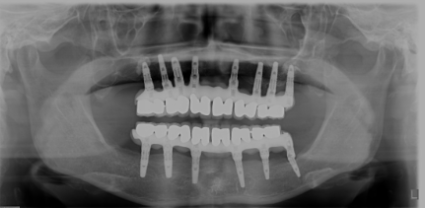

多数歯欠損のインプラント治療の症例(うえだ歯科)

| 主訴 | 歯がグラグラで噛むことができない。インプラントをして欲しい。 |

| 治療内容 | 歯周病で骨の吸収が重度で保存不能なため抜歯、仮の入れ歯を作り、6ヶ月の抜歯窩の治療の後に、インプラントのCTによる診査診断を行い、下顎に6本インプラント埋入と同時に仮歯を入れる。その後、上顎は8本のインプラント埋入と同時に仮歯を入れる。左右上6はソケットリフトによる上顎洞拳上術を行う。その後免荷期間6ヶ月待ってセラミックを用いた上部構造作製、装着しメンテナンスに移行する。 |

| 治療費 | 9,000,000円(税込) |

| 治療期間 | 2年3ヶ月 |

| 治療回数 | 90回 |

| 想定されたリスク | 重度の歯周病により無歯顎になったため、プラークコントロール不良による、術後のインプラント周囲炎が懸念される。歯冠の部分はセラミックなため欠ける可能性がある。 |